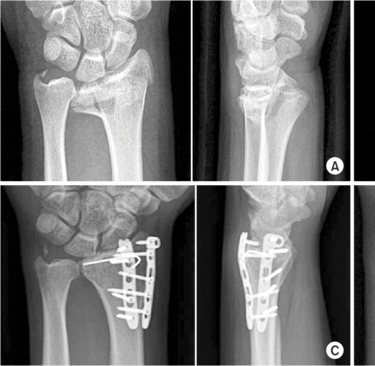

Radiografías: Son la herramienta principal para visualizar las fracturas de muñeca.

Tomografía Computarizada (TC): Puede proporcionar imágenes más detalladas si la radiografía no es concluyente.

Reducción Abierta y Fijación Interna (ORIF): Este procedimiento implica la colocación de placas y tornillos para mantener los huesos en su lugar.